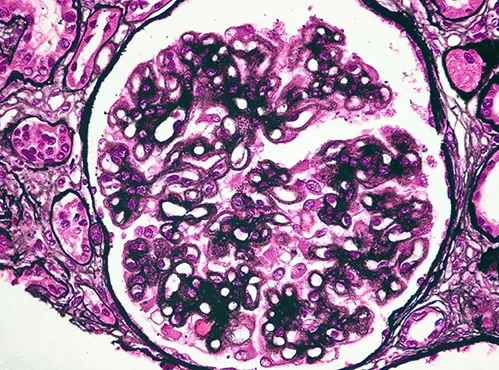

Injúria Renal Aguda (revisão Lancet 2025)

Injúria Renal Aguda (revisão Lancet 2025)